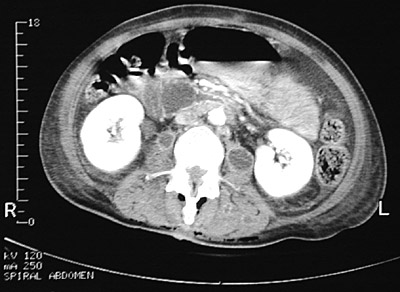

These pelvic CT scan views above and below reveal the presence of both larger abscesses as well as smaller abscesses with ring enhancement seen in paraspinal muscles.